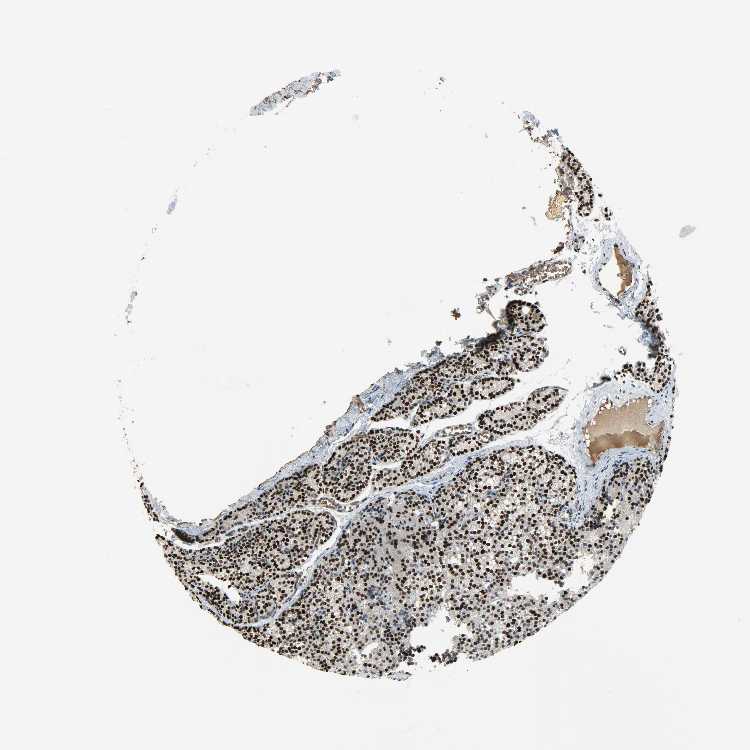

TISSUE PRIMARY DATA PARATHYROID GLAND Show tissue menu

PARATHYROID GLAND - Antibody stainingi

Antibody staining in the annotated cell types in the current human tissue is reported as not detected, low, medium, or high, based on conventional immunohistochemistry profiling in selected tissues. This score is based on the combination of the staining intensity and fraction of stained cells.

Each image is clickable and will lead to virtual microscopy that enables deeper exploration of all samples and also displays staining intensity scores, fraction scores and subcellular localization as well as patient and tissue information for each sample.

Antibody HPA069985Antibody CAB005883Antibody CAB078687Antibody CAB080398

Glandular cells HighHighNot detectedHigh